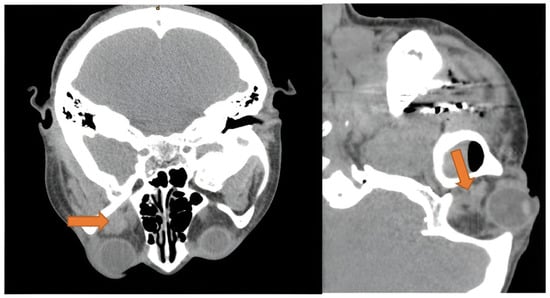

3.4.1. Orbital Cellulitis and Abscess

3.4.2. Orbital and Subcutaneous Emphysema

Orbital Emphysema